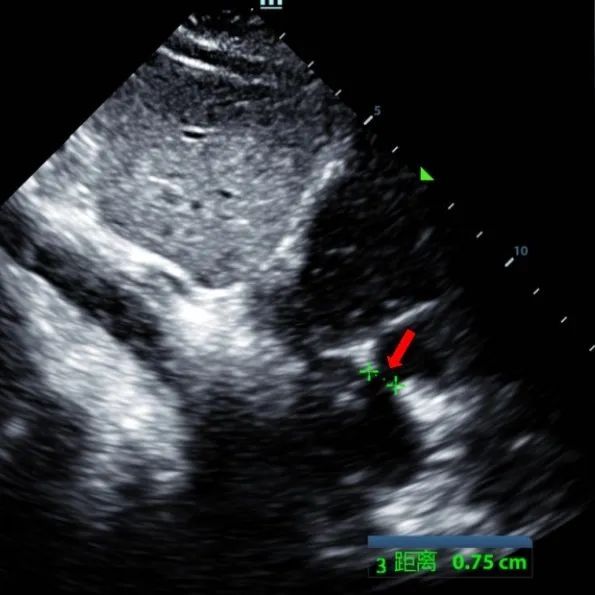

Ein 9-jähriger Mann mit secundum ASD (7,5-7,9mm) wurde mit einem MemoSorb-BDASD-I 12-mm-Okk luder und einem 12F-Fördersystem behandelt. Vor dem Eingriff wurden keine Komplikationen oder Komorbiditäten festgestellt.